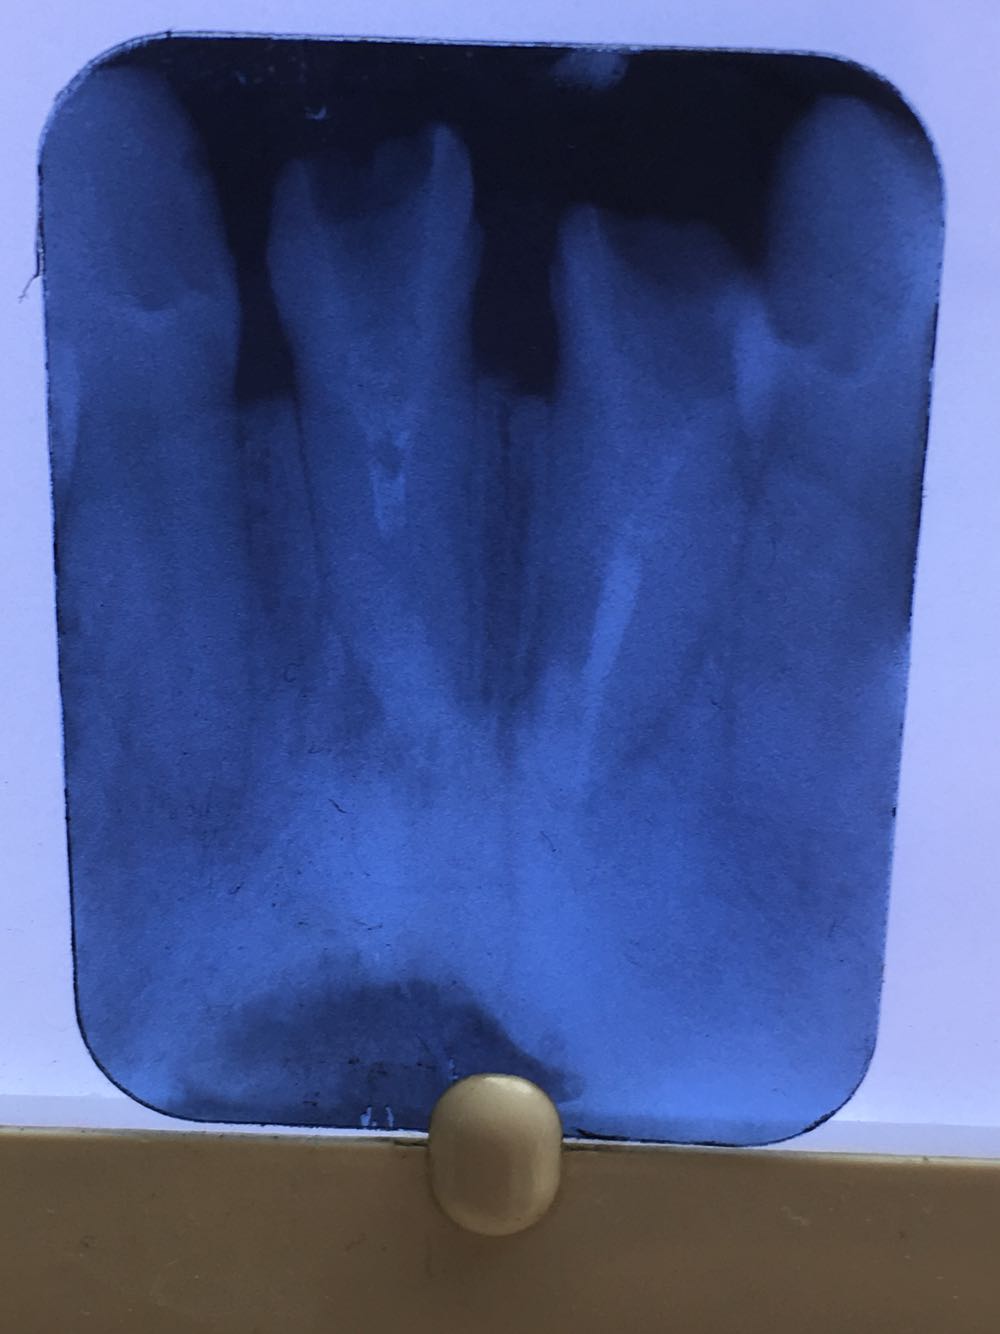

查:11,21残根无松动,根管内空虚。既往曾镶桩冠牙十多年。X线片示未做根管治疗,11根内可见约3毫米充填物。

11.21残根;治疗方案拟行根管治疗后桩冠修复

上前牙残根在牙根長度足够和无松动的情况下应尽量保留,行桩冠修复是较好的治疗方法